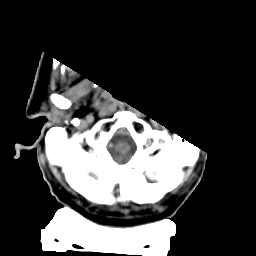

Meningioma: Roentgen-ray CT #2 -- Slice #0

[Home][Help][Clinical] Slice 0